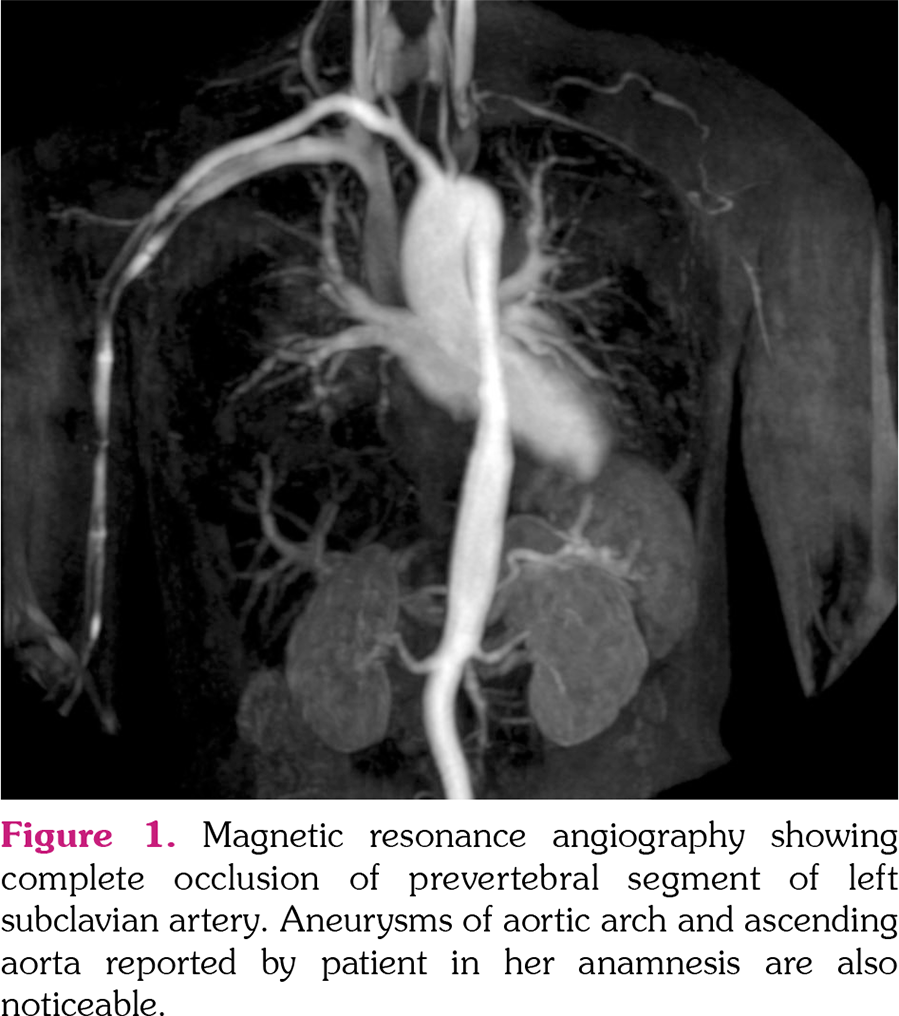

Takayasu arteritis (TAK) is a rare systemic vasculitis affecting large vessels. Disease onset is insidious, with nonspecific early symptoms contributing to a significant diagnostic and therapeutic delay. TAK usually starts in females of reproductive age; hence, planning and management of pregnancy are important issues. Comprehensive evaluation and a multidisciplinary approach to these patients in a tertiary care center can lead to a favorable outcome for the mother and fetus. Unfortunately, still up to one‐ third of TAK patients may be advised against pregnancy by their clinicians.[1] Here, we report the case of a 32‐year‐old female patient (gravida 2, para 1, 52 kg, body mass index 18.6 kg/m[2]) with a history of aortic arch and ascending aorta aneurysm. In 2015, the patient had a term vaginal delivery of a fetus with intrauterine growth restriction (birth weight 1900 g). Postpartum period was complicated by the onset of posterior reversible encephalopathy syndrome, six hours after delivery. Later, neurological follow‐up was negative. She reported to be in good health afterward. In April 2019, she was admitted to Obstetrics and Gynecology departments at 16 weeks of the gestation, complaining of persistent fever unresponsive to paracetamol, paresthesia, and claudication of the left arm and arterial hypertension. Blood tests showed increased acute phase reactants and normal liver and kidney function. A magnetic resonance angiography was carried out, evidencing absence of flow signal in the prevertebral segment of the left subclavian artery with revascularization through the vertebral artery (Figure 1). She was referred to a rheumatologist and TAK was diagnosed (American College of Rheumatology classification criteria were fulfilled because of typical disease onset at ≤40 years, presence of abdominal bruit, left arm claudication, and specific arterial abnormalities).[2] The therapeutic approach consisted of azathioprine 50 mg twice daily and daily prednisone 50 mg with 6.25 mg reduction per week until reaching a maintenance dose of 6.25 mg daily while alpha‐ methyldopa 500 mg twice daily was administered to control hypertension. The subsequent course of pregnancy proceeded without further complications. Fever resolved three days after glucocorticoids initiation whereas acute phase reactants decreased to normal range. The patient underwent elective caesarean section at 37 weeks of gestation. The postoperative course was regular. Arterial hypertension resolved after the birth. She continued to receive azathioprine at the same dose as it was suitable with breastfeeding. At three‐month follow‐up, no disease flare occurred. Successful pregnancy outcomes for both mother and fetus are known for TAK patients.[3] Current evidence indicates that pregnancy does not influence TAK disease activity, although clinicians should be familiar that severe pregnancy‐ related complications, such as hypertension, preeclampsia/eclampsia, prematurity, intrauterine growth restriction as well as inflammatory flares have been reported.[1,4] Of note, their occurrence varies widely between populations;[1] consequently, uncertainties and fear on the part of both patients and counseling physicians may have an impact on family planning in TAK.[1] This case offers food for thought capable of informing TAK management in pregnancy. Concerning counseling, patients should be advised to plan pregnancy during states of low disease activity.